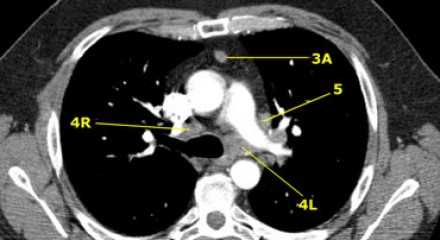

4L. Левые нижние паратрахеальные лимфатические узлы

4L узлы расположенные слева от левой стенки трахеи, между горизонтальными линиями проведенными касательно верхней стенке дуги аорты и линией проходящей через левый главный бронх на уровне верхнего края верхнедолевого бронха. Они включают паратрахеальные узлы расположенные кнутри от артериальной связки.

Узлы 5 группы (аортопульмонального окна) расположены кнаружи от артериальной связки.

На левом изображении над уровнем легочного ствола представлены нижние паратрахеальные узлы слева и справа, так же здесь представлены узлы 3 и 5 групп.

Изображение слева выше уровня карины. Слева от трахеи 4L узлы. Обратите внимание что они расположены между легочным стволом и аортой, но не в аортопульмональном окне, потому что они лежат медиальнее артериальной связки. Лимфатические узлы латеральнее легочного ствола относятся к 5 группе.

- 5. Субаортальные лимфатические узлы

- Субаортальное или аортопульмональное окно расположено кнаружи от артериальной связки и проксимальнее первой ветви левой легочной артерии и лежит в пределах медиастинальной плевры.

- Парааортальные лимфатические узлы лежат кпереди и кнаружи от восходящего отдела аорты и между верхним и нижним краями дуги аорты.